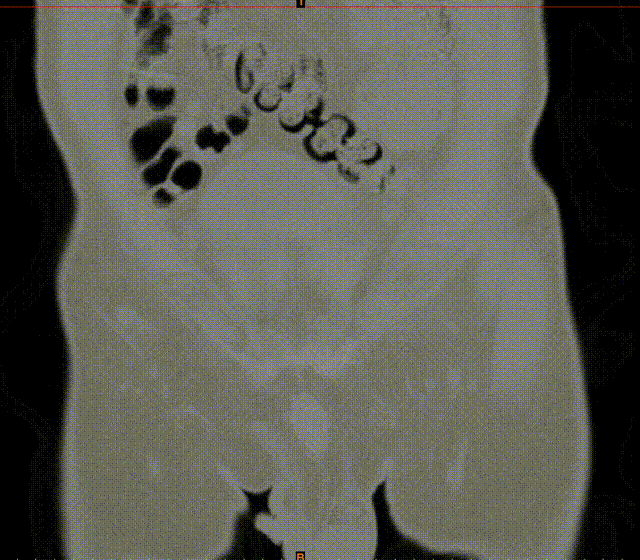

张洪彬医生对患者骨盆三维CT进行了术前虚拟仿真,辅助术者规划骨折复位过程及通道螺钉的置入长度、角度及方向。在患者伤后2周内,由刘利主任主刀,采取单一Kocher-Langenbeck 入路手术入路,术中仔细对坐骨神经及旋股内侧动脉进行了保护,降低了远期发生神经损伤及股骨头缺血性坏死发生风险,完成复位后,应用两块重建钢板及一枚通道螺钉就完成了复杂骨折的固定。术后复查DR及CT骨折复位理想,内固定位置满意,没有发生螺钉进入关节腔的情况。患者得到了早期功能康复锻炼的有利条件。患者现已顺利出院。